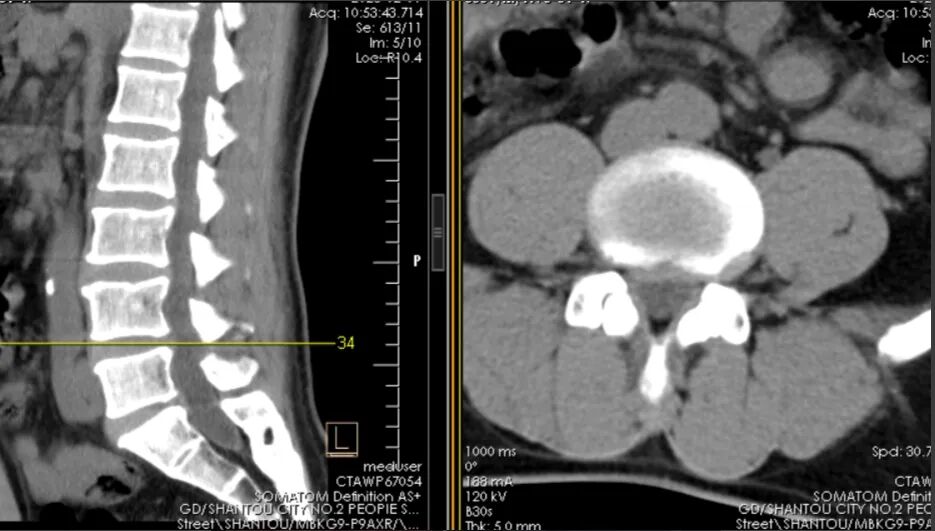

病例二:董先生(化名)是一名中年的患者,因腰椎间盘突出、椎管狭窄导致多年腰腿痛,严重影响工作和生活。期间反复保守治疗,但效果不佳,入院后经我院骨科团队评估后,决定为其实施全麻下UBE髓核摘除、减压融合内固定术。术后第2天患者佩戴腰围下床活动,腰腿痛完全消失,手术效果显著。

术前CT

术后CT